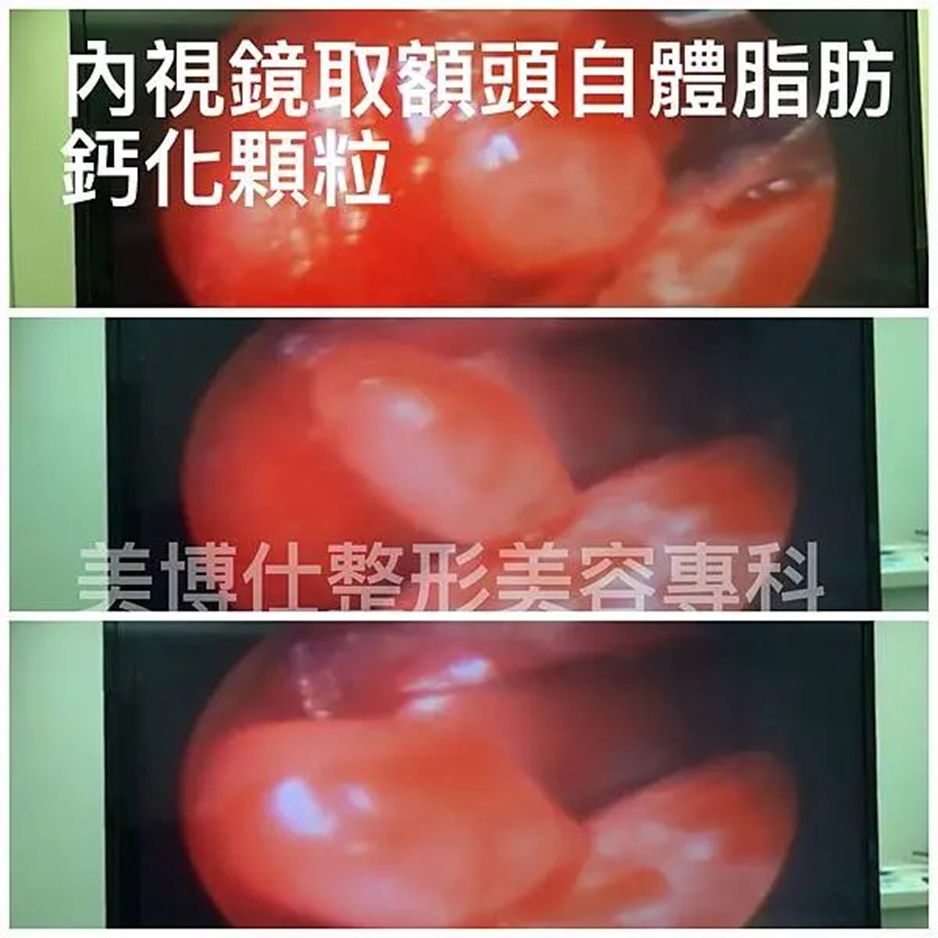

下圖: 3D電腦斷層掃描下發現填充注射後的材料不平均的堆疊

下圖標示紅色區為太陽穴注射脂肪三年後的下移腫塊外觀。

2. 注射自體脂肪–同樣因咀嚼肌活動,與脂肪細胞特性吸收率高,可能須多次注射。易發生不平凹凸(吸收不均或鈣化顆粒),再者脂肪太陽穴常造成頭大厚重感,求美者擔心的饅化😅(下圖)。讓臉型不夠精緻。

內視鏡下的外觀:

墊片:https://www.youtube.com/shorts/SuKsXisCoTE

注射填充:https://www.youtube.com/shorts/skjjnkVdwOA